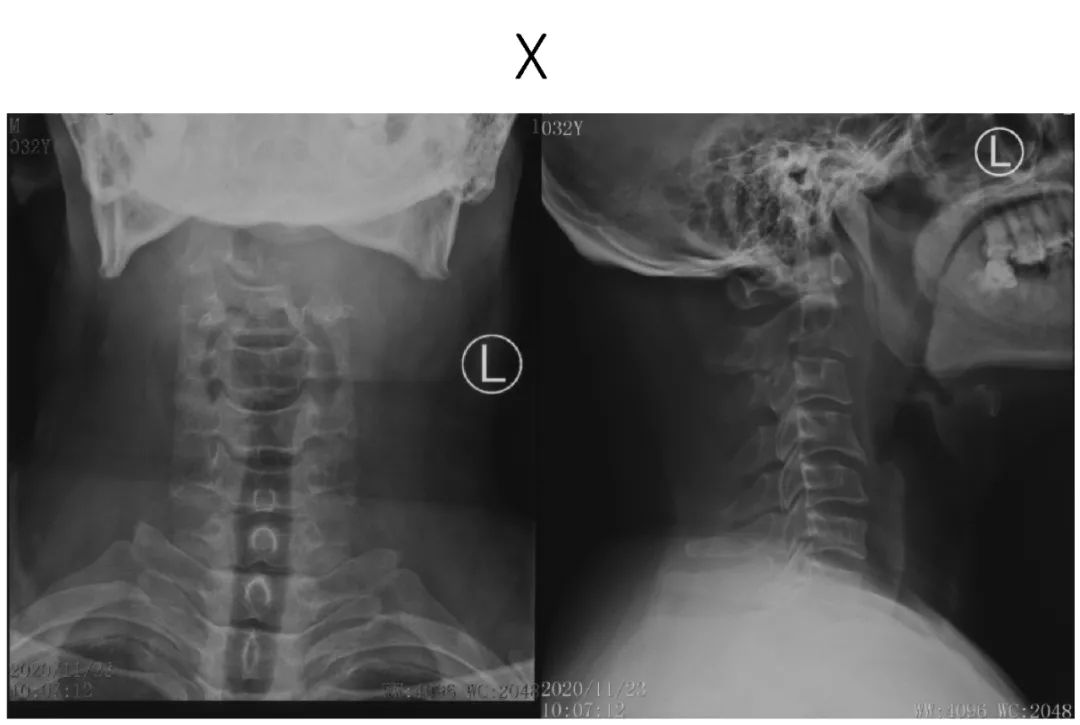

病史:male, 63 y/o

Neck pain for 3 months

影像资料:

诊断:C2椎体肿瘤